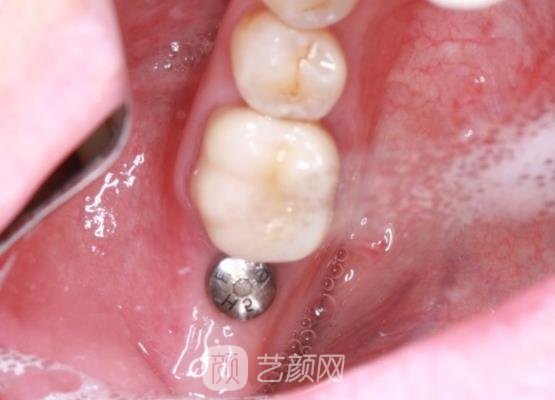

种植牙手术案例:

然后医生就帮我进行了手术,手术过程中因为采用了麻药的处理,所以我也没有感觉到剧烈的疼痛感,短短几个小时以后手术就结束了,也没有浪费我很多的时间,这是我没有想到的。

刚结束手术时,我的牙龈处还存在着一些肿胀的情况,有着很疼的感觉,医生随后对我的牙龈情况进行了检查,然后给我开了一些消炎药让我定时服用。

几个月以后,我的牙齿已经恢复好了,成果也是很自然的,就像是我自己的牙齿一样,口腔里面也没有一些异物的感觉,我的整个外貌条件都因为牙齿问题得到解决而提升了很多,果然手术是有成果的。